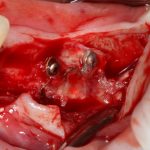

Откроем область операции и посмотрим, что там:

Вроде как, всё неплохо. Наверное, можно поставить имплантаты?

ну, или как-то так: